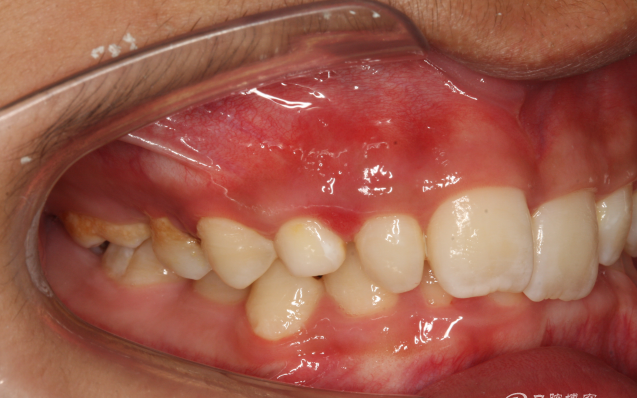

圖2.右側位咬合影像:乳尖牙滯留

QQ圖片20150710153724.png